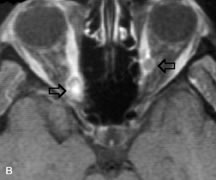

PATIENT PREPARATION Before MRI is performed, patients must be screened and prepared to avoid the potential hazards associated with the strong magnetic field. Patients who have ferrous aneurysm clips or cardiac pacemakers, who depend on life-support equipment, or who retain a possible metallic intraocular foreign body are not candidates for this imaging modality. MRI cannot be performed on obese patients who cannot fit into the bore of the magnet. Patients who are claustrophobic may not tolerate a prolonged period of study within the confines of the magnet, whereas others might do well if given a mild sedative. All worn metallic objects (e.g., necklaces, watches) should be taken off, credit cards set aside, and eye makeup removed before entering the room containing the magnet.5,20,34,35,36 NORMAL ORBITAL ANATOMY T1-weighted images provide the best anatomic details of the orbit because they display superior contrast resolution between normal structures (see Fig. 8). The vitreous has a long T1, resulting in an intermediate signal similar to brain, whereas the crystalline lens and sclera appear dark because of a longer T1 and short T2. The extraocular muscles, like all skeletal muscles, demonstrate a moderately long T1 and short T2 and highly contrast with the intense signal of the surrounding orbital fat (adipose tissue has an extremely short T1). The lacrimal glands appear as mottled areas of reduced intensity of the signal from the orbital fat in the lacrimal fossa. The optic nerves are seen with the same signal intensity as brain white matter and are hypointense relative to the orbital fat because their Tl is longer than the Tl of fat but shorter than the Tl of water. Cortical bone is not well delineated because it contains little free water, yielding minimal signal in MRI, and thus appears dark on all pulse sequences. This feature explains why MR images of the orbital apex and intracanalicular portion of the optic nerves are superior to comparable CT scans. Partial volume averaging of the bones in these regions obscures soft tissue details on CT images, whereas MRI reveals the signals only from the soft tissue structures with no cortical bone input. Bone marrow, on the other hand, is seen as a relatively intense signal because of its high fat content (see Fig. 8).37,38 T2-weighted pulse sequences are not ideal for imaging normal anatomy; however, they are particularly useful in revealing pathologic conditions (see Fig. 9). T2-weighted studies are most easily recognized by a bright vitreous signal. ORBITAL DISEASES Vascular Lesions Cavernous hemangiomas appear as well-circumscribed, smooth, usually intraconal masses that are isointense to muscle on T1-weighted images and hyperintense on T2-weighted images (Fig. 12). Patchy early enhancement is typically followed by diffuse, more homogeneous enhancement.39 The internal architecture of the mass, including septation and internal vasculature, may often be appreciated with high-quality orbital imaging.40 Lymphangiomas consist of ectatic vascular channels within a connective tissue stoma with varying degrees of lymphoid cellularity. On MRI, these tumors are typically poorly circumscribed, multicompartmental, and heterogeneous, often showing cystic dilations with fluid levels (Fig. 13). The signal characteristics within lymphangiomas vary considerably, reflecting cystic and solid components and the varying paramagnetic characteristics of blood at different stages of degradation.40–42 Acute hemorrhage appears hypointense on both T1- and T2-weighted formats. Methemoglobin present in subacute hemorrhage (3 to 14 days) leads to hyperintense signal on both T1- and T2-weighted images.41 A small percentage of lymphangiomas appear radiologically indistinct from orbital cavernous hemangiomas.43 Orbital varices are venous malformations that expand with increased systemic venous pressure, such as with Valsalva maneuvers. Because rapid acquisition of images during a Valsalva maneuver is important in imaging such a lesion, conventional or spiral CT is currently the modality of choice.44 MRI is an excellent modality for demonstrating enlargement of the cavernous sinus and dilation of the superior ophthalmic vein in patients with high-flow carotid-cavernous fistulas (Fig. 14).37MRA may be helpful in the evaluation of the venous outflow pattern. The rapidly flowing blood in these vascular structures carries the excited protons out of the section before they can be imaged, resulting in their dark appearance.5 In low-flow dural arteriovenous malformations, MRA may help define the arterial feeding vessels.45 Neural Lesions MRI is more effective than CT in delineating the intracranial optic nerves, chiasm, and optic tracts and, for this reason, is the preferred imaging modality in the evaluation of optic nerve disorders. The spatial relationships and image contrast of the orbital tissues with intraorbital optic nerve tumors is comparable between the two imaging modalities. The normal nerve is isointense to brain and appears enlarged and kinked owing to infiltration of an optic nerve glioma on T1-weighted images. Gliomas appear hyperintense on T2-weighted images and may be heterogeneous owing to cystic areas within the tumor. Contrast enhancement is variable.46 Intraorbital and intracranial optic nerve sheath meningiomas are usually isointense to cortical gray matter on Tl-weighted images and remain isointense on proton density studies (Fig. 15). Gd-DTPA is useful in delineating the intracranial extension of optic nerve meningiomas.7,47 The hyperostosis of bone and calcification associated with meningiomas are not demonstrated as well on MRI studies as on CT scans.20,37 Gd-DTPA–enhanced MRI also appears promising in the study of the permeability of the blood–brain barrier in selected optic neuropathies.22,48 MRI may reveal an enlarged optic nerve and some degree of contrast enhancement in cases of optic neuritis.49 Muscle Disorders Extraocular muscle enlargement in patients with thyroid-associated orbitopathy is demonstrated equally well with CT and MRI studies. However, the superior tissue contrast on MR images reveals better details of the relationships of the optic nerve to the thickened muscles at the orbital apex (Fig. 16).50 In addition, MRI may be able to differentiate between muscles that are enlarged as a result of edema and active inflammation and those enlarged because of fibrosis by their T2 relaxation times.21 Quantitative MRI was not found to be accurate in predicting the success of low-dose orbital irradiation.51 However, a muscular index relating the diameters of the rectus muscles to the bony orbital dimensions was useful in predicting optic nerve compression.52 MRI is also effective in imaging orbital tumors of mesenchymal origin, such as rhabdomyosarcoma, particularly in the assessment of extension into the anterior and middle cranial fossae (Fig. 17).37 The lack of any pathognomonic radiologic features necessitates rapid orbital biopsy when rhabdomyosarcoma is suspected. Osseous Lesions In general, CT is the imaging modality of choice when details of quantity and quality of bone are needed; however, abnormalities of bones can be detected indirectly by MRI. Cortical bone appears black (signal void) on MR images because of its low proton density and free-water content. The absence or discontinuity of the signal void of the orbital walls may represent bony destruction or fracture. Hyperostosis associated with prostate metastases or meningioma is visualized as areas of black smudging.50,53 Diseases in which the bone is replaced by pathologic tissues with a high free-water content, such as fibrous dysplasia, are well demonstrated on MRI. An intermediate signal intensity on T1-weighted images and hypointense signal on T2-weighted images is representative of fibrous dysplasia. Enhancement on post–Gd-DTPA MR scans is seen and is more evident in areas that are less mineralized.54 Cystic Lesions Dermoid cysts appear as rounded, well-defined lesions typically contiguous with an orbital bony suture. The high-intensity signal on T1-weighted images is attributed to the sebaceous-produced lipid contents (Fig. 18).31,50 Mucoceles may demonstrate a hypointense or hyperintense signal on MR images, depending on the concentration of proteinaceous or inflammatory fluid components. The integrity of the bony walls of the expanded sinus cavities cannot be assessed on MR as well as by CT.37,50,55,56 A high-signal intensity on Tl- and T2-weighted images is characteristic of orbital chronic hematic cysts because of the blood-breakdown products within the cysts.57 Trauma Although soft tissue relationships are usually better demonstrated on MRI, the evaluation of craniofacial bony trauma is preferable with CT. For example, prolapse of orbital fat through a fracture site and hemorrhage of adjacent tissues are demonstrated in an MR image, but the actual fractured bone is not imaged. Three-dimensional MRI of the orbit in subacute trauma has been described,58 although its precise role is not currently established. MRI has been suggested to be superior to CT in detecting intraorbital wooden foreign bodies.59,60 In a series of penetrating orbital injuries with organic foreign bodies, however, MRI was able to identify the foreign body in only four of seven cases.61 With an in vitro model for wood foreign body, McGuckin and colleagues concluded that CT was the imaging modality of choice.62 A careful history and, in selected cases, plain films to rule out a metallic foreign body are crucial before MRI is considered in patients with periocular trauma. MRI is particularly helpful in the detection and characterization of subperiosteal hematomas of the orbit (Fig. 19). They are most commonly seen in the subperiosteal space of the superior orbit as well-defined masses following a traumatic injury. The signal intensity varies depending on the acute, subacute, or chronic nature of the hematoma, based on the stage of blood degradation. Fresh hemorrhages are hypointense on T1-weighted images and hyperintense on T2 images. Hematomas that are 1 to 7 days old are hypointense on both T1- and T2-weighted images. T1-weighted images of hematomas more than a week old are hyperintense due to the oxidation of deoxyhemoglobin to methemoglobin, whereas the T2 images remain hypointense.63 Metastatic Tumors Breast carcinoma metastatic to the orbit has been demonstrated to be hypointense to the surrounding orbital fat on T1-weighted studies and hyperintense on T2-weighted images and has an affinity to the extraocular muscles (Fig. 20).50,64 The MRI characteristics of prostate carcinoma metastatic to the orbit have been described as involving the greater and lesser wing of the sphenoid, orbital roof, and optic canal. Diffuse bone hypertrophy with isointense or slightly hyperintense tissue on T1-weighted images represents the osteoblastic carcinomatous bone infiltration. Contrast enhancement is variable on T1-weighted and fat-suppressed images.65 Most other metastatic tumors also have a lower intensity signal on T1-weighted images and appear to displace or infiltrate normal orbital structures; however, their signal characteristics are variable on T2-weighted MR images.66 Many metastatic tumors demonstrate bright contrast enhancement with Gd-DTPA. Infectious Disorders MRI findings of preseptal and orbital cellulitis typically include increased signal intensities on T2-weighted images of the eyelids and orbital fat, respectively, due to the increased water content of the tissues. Since most cases of bacterial orbital cellulitis are associated with paranasal sinusitis, hyperintense signals of the affected sinuses may also be found on T2-weighted images as well as enhancement of polyps and granulation tissue on postgadolinium T1-weighted MR images. Subperiosteal abscess formation may occur due to contiguous spread of infection from the paranasal sinuses and appear on MRI as an area of intermediate signal on T1-weighted and proton-weighted MR images. The abscess may appear slightly hyperintense compared with muscle on T2-weighted scans with the necrotic contents having the greatest intensity.67 MRI and MRV are more sensitive than CT in revealing cavernous sinus thrombosis. Engorgement of the cavernous sinus, extraocular muscles, and ophthalmic veins is seen with hyperintensity of the thrombosed sinuses evident on all pulse sequences. The enlarged, thrombosed superior ophthalmic vein appears less hypointense than the normal contralateral ophthalmic vein, and hyperintensity within the lumen of the vessel may be seen on T1- and T2-weighted MR images.68 Inflammatory and Lymphoproliferative Lesions Inflammatory conditions of the orbit, both idiopathic (inflammatory pseudotumor) and those of known causes, have been found to be hypointense to fat and isointense to muscle on Tl-weighted studies and isointense or slightly hyperintense to fat on T2-weighted images (Fig. 21).50,64,69 The more fibrous or sclerosing varieties have less signal intensity on T2-weighted images. Marked enhancement is seen in pseudotumor infiltrates after gadolinium administration.70 The same signal characteristics are demonstrated in patients with Tolosa-Hunt syndrome, with mass lesions seen in the cavernous sinuses and orbital apices.71 Lymphomas have MRI characteristics similar to those of inflammatory lesions in that they are hypointense to fat and isointense to muscle on T1-weighted images (Fig. 22). They may appear hyperintense to fat on T2-weighted images, perhaps owing to less fibrosis than that seen in orbital inflammatory pseudotumor, although this is not a consistent finding.31,50,66 Lymphoid tumors typically enhance moderately after contrast injection. Unfortunately, studies have shown that tumor density and homogeneity are similar between inflammatory and malignant orbital infiltrates, and MRI cannot differentiate these lesions.72,73 Lacrimal Gland Tumors Lacrimal gland lesions present special problems in diagnosis and management. Pleomorphic adenoma (benign mixed tumor) should not be biopsied, but rather excised in toto. On the other hand, for lymphoma and inflammatory infiltrates, incisional biopsy is more appropriate than complete excision of the lacrimal gland. Thus, preoperative clinical and radiologic evaluation are especially crucial in planning appropriate surgical management. Pleomorphic adenomas demonstrate long T1 and T2 signal characteristics. They may show heterogeneity on T2-weighted images74 and moderate to marked enhancement with contrast.75 Signal characteristics of adenoid cystic carcinoma include hypointensity to fat on T1-weighted images, hyperintensity to fat with increased T2 weighting, and isointensity to fat on proton density-weighted studies (Fig. 23).31,75 Secondary bony alterations of the lacrimal fossa associated with lacrimal gland tumors, such as remodeling (benign mixed tumor) or destruction (adenoid cystic carcinoma), are seen indirectly on MR images; however, bone windows on CT scans provide better delineation of these changes. In contrast to the round or globular appearance of benign or malignant epithelial tumors of the lacrimal gland, lymphoproliferative tumors usually appear to be molding or draping onto the globe and the surrounding bony orbit. LACRIMAL DRAINAGE SYSTEM DISORDERS MRI with surface coils provides excellent spatial resolution and tissue-specific signal intensities of the lacrimal drainage system. These parameters have been found useful to more accurately demonstrate the extent of lesions in the lacrimal sac and differentiate long-standing mucoceles from solid tumors than CT.76 Physiologic studies in patients with tearing disorders now include MR dacryocystography, in which Gd-DTPA is either placed topically in the conjunctival fornix or injected by cannulation into the lacrimal sac. They provide a detailed morphologic and functional analysis of the lacrimal excretory system; however, they are no more sensitive than digital-subtraction dacryocystography or CT dacryocystography.77–79 INTRAOCULAR TUMORS On MRI, uveal melanomas have a typical appearance that helps to differentiate them from other primary and secondary intraocular tumors as well as choroidal detachments. Pigmented melanomas are hyperintense on Tl-weighted images, hypointense on T2-weighted studies, and hyperintense on proton density–weighted examinations (Fig. 24).30,31,50,80–82 These signal characteristics have been attributed to the paramagnetic properties of melanin because of stable free radicals that shorten the T1 and T2 relaxation times. Moderate enhancement is seen on postgadolinium T2-weighted images. Gadolinium-enhanced T1-weighted images are particularly sensitive in detecting choroidal melanomas.83 MRI may be less sensitive in detecting extrascleral extension of tumor than echography performed by an experienced ultrasonographer.84 Tumors metastatic to the choroid are hyperintense on T1- and T2-weighted images.24 The signal characteristics, however, may be similar to those seen with choroidal melanoma. Choroidal hemangiomas, on the other hand, have an intermediate signal on T1-weighted sequences and become hyperintense on T2-weighted images50 as well as proton density–weighted images.81 Retinoblastomas display moderate signal intensity on T1-weighted studies and a low signal on T2-weighted images.31,80,85 Calcification can be easily detected by CT and ocular ultrasonography but is not imaged by MRI.25,50 The presence of optic nerve involvement is best evaluated by MRI. ACQUIRED ANOPHTHALMIA When an eye is removed owing to tumor or trauma, an implant is typically placed in the intraconal space. MRI may be useful in defining the size, shape, and position of such orbital implants.86 Porous hydroxyapatite or polyethylene implants are preferred by many surgeons performing enucleation or evisceration. A porous implant offers the possibility of supporting a motility coupling peg to increase the movement of the overlying prosthesis. MRI with contrast is used by some surgeons to evaluate the degree of fibrovascular ingrowth in hydroxyapatite87 and porous polyethylene88 implants prior to motility peg placement. |